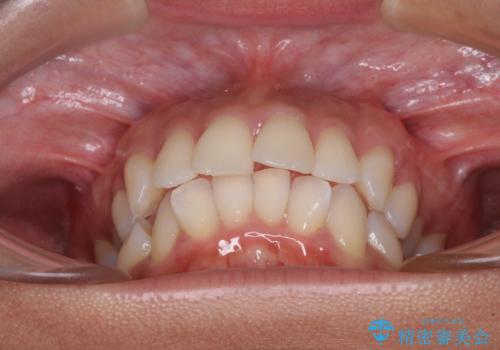

- 下唇が突き出るような口元の突出感が気になるとのことで来院された患者様です。

上下顎ともに前突した歯列であったので、上下ともに左右の第1小臼歯4本を抜歯し、ワイヤー装置にて矯正治療を行うこととしました。

抜歯スペースに前歯を移動させることで歯の突出感が改善され、非常に唇が閉じやすい仕上がりとなりました。